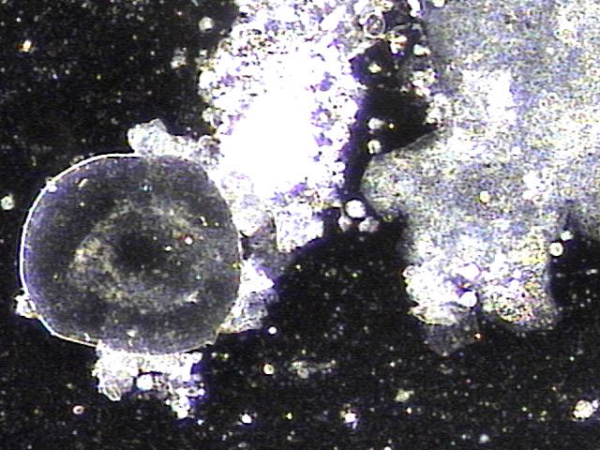

주 2회 전립선의 표적 치료중 전립선액과 정낭액 그리고 전립선 결석과 정관등에 침범하여 퍼지고 있는 균의 배양과 항생제 민감도 검사를 하기위해 표적 치료후 배출된 전립선액의 현미경 검사 자료입니다.

탈락된 상피세포 덩어리와 혈정액과 전립선 결석과 전립선암의 전암병변 의심되는 자료입니다.

This is a microscopic examination of prostatic fluid discharged during biweekly targeted prostate therapy. The sample was obtained to conduct bacterial culture and antibiotic sensitivity testing for organisms invading and spreading through the prostatic fluid, seminal vesicle fluid, prostate calculi, and vas deferens. The findings include clusters of desquamated epithelial cells, hematospermia, prostatic calculi, and features suspicious for precancerous lesions of prostate cancer.